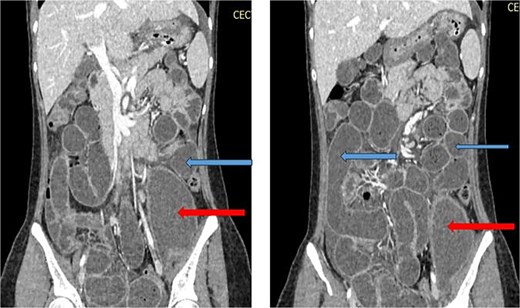

X-ray abdomen showed dilated small bowel loops with faecal loading (Fig. 1). Ultrasound abdomen/pelvis revealed dilated small bowel loops with to-and-fro peristalsis, suggestive of small bowel obstruction. Contrast-enhanced computed tomography (CT) abdomen/pelvis revealed distal ileal thickening causing obstruction, a left iliopsoas abscess communicating with a paravertebral abscess (L5–S2), and erosion of the L5 vertebral body (Figs 2 and 3).

CT abdomen/pelvis with contrast, upper arrows showing dilated small bowel loops and lower arrrows showing collection in left psoas muscle.